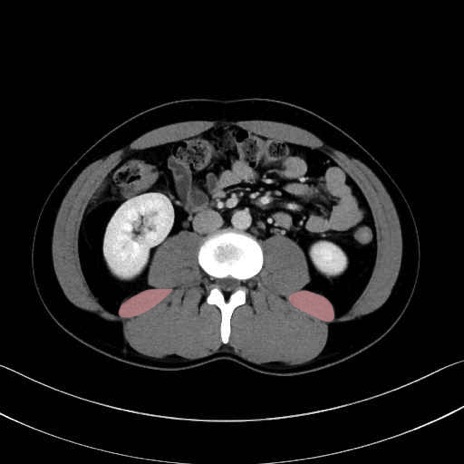

2. 腸腰筋群と骨盤底筋

大腰筋 (Psoas major)

腸骨筋 (Iliacus)